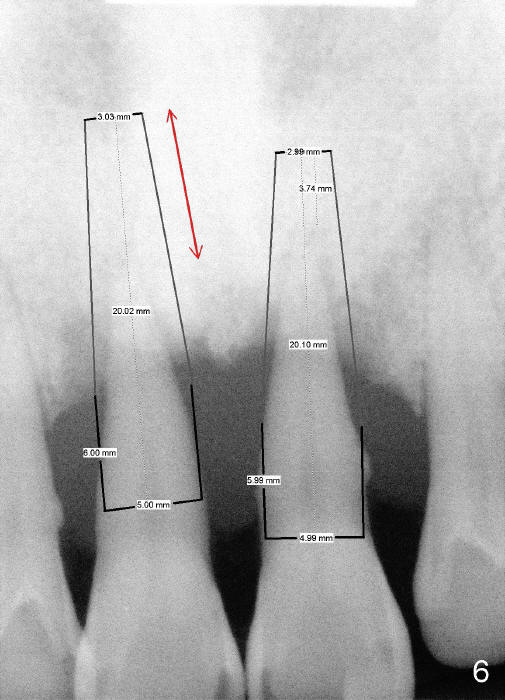

A 44-year-old man has advanced periodontitis (Fig.1,2). The infection resolves substantially 5 days post scaling & root planing (Fig.4,5). The two centrals have severe bone loss (Fig.3) and are going to be replaced by 5x20 mm implants (Fig.6).